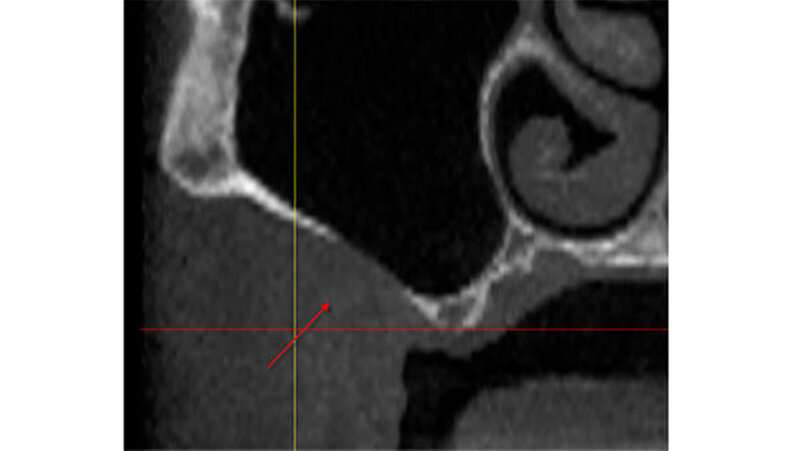

So planten wir für den März 2014 einen Sinuslift mit Augmentation und die Insertion zweier Implantate. Während dieses Eingriffs wurde ein Defekt in der buccalen Sinuswand deutlich sichtbar. Anscheinend bindegewebig war die Schneider`sche Membran durch den Knochendefekt mit der Wangenschleimhaut verbunden (Abbildung 1). Nach Durchtrennung des Gewebes und einer Abdeckung des Durchgangs mit einer resorbierbaren Membran wurde synthetisches Knochenersatzmaterial eingebracht und die Operation wie ursprünglich vorgesehen durchgeführt. Seither ist die Patientin beschwerdefrei.

Die vor der geplanten Implantation gesichtete DVT hatte zunächst keinen knöchernen Defekt ausgewiesen. Erst bei nochmaligem und kompletten "Durchscrollen" aller Aufnahmen wurde der Defekt sichtbar (Abbildungen 2 bis 5).